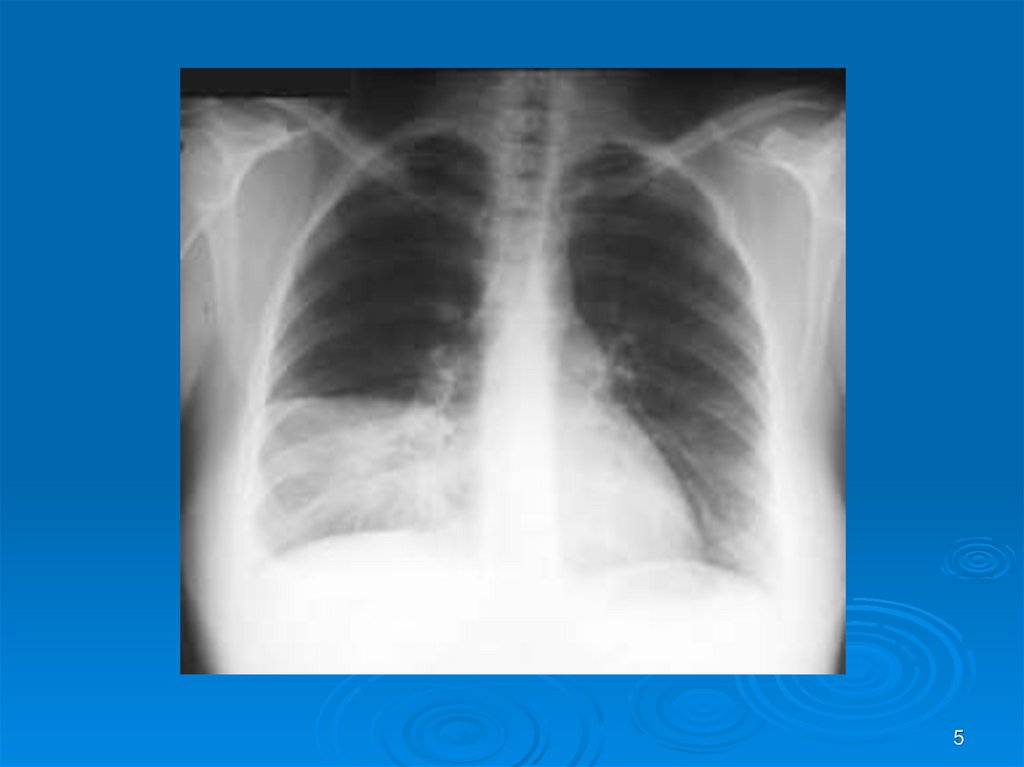

5.

5